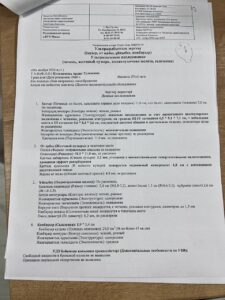

Кульжанова Ардак Туленовна 31 декабря 1960 года рождения, в марте 2024 с кровотечением поступила в ТОО » Национальный научный онкологический центр», где был выставлен диагноз » эхинококкоз печени».

С марта по ноябрь 2024 года принимала противопаразитарные, иммуностимулирующие и восстанавливающие функции внутренних органов препараты, в купе с соблюдением необходимой диеты и ходьбы. На сегодня 21 ноября 2024 года, чувствую себя отлично ( самочувствие хорошее, энергия отличная, посветлела и исчезают пигментные пятна на лице и ТД).

На УЗИ от 06.11.2024 наблюдается положительная динамика.